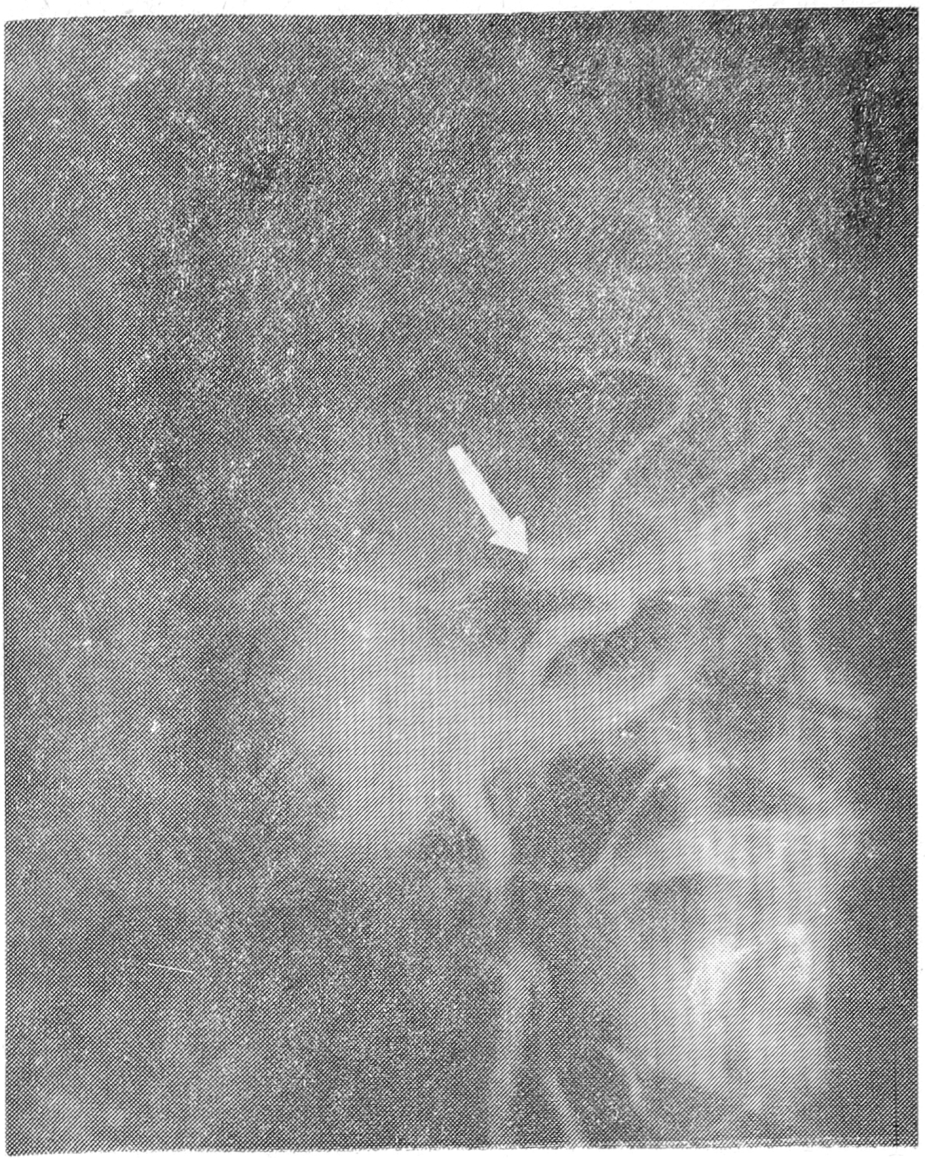

30/10-1984 г. выполнена церебральная ангиография. На левосторонних каротидных ангиограммах в артериальной фазе отмечены конусовидное сужение супраклиноидной части левой внутренней сонной артерии и окклюзия левой средней мозговой артерии в начальной части с развитием бессосудистой зоны в ее бассейне (рис. 1).

Рис. 1. Наблюдение 1-е.

Каротидная ангиография. На ангиограммах в артериальной фазе определяется сужение супраклиноидной части внутренней сонной артерии и начального отрезка задней мозговой артерии (стрелка). Средняя мозговая артерия не контрастируется.

В проекции базальных ганглиев видна нежная аномальная сосудистая сеть, напоминающая клубы сигаретного дыма. В поздней артериальной фазе — ретроградное заполнение бассейна средней мозговой артерии через аномальные анастомозы между дистальными ветвями левой средней мозговой артерии и передней и задней мозговыми артериями. Дополнительно выполнена аортография, которая позволила обнаружить стеноз левой плечевой артерии в проекции ее отхождения от аорты и атипичное отхождение левой позвоночной артерии от аорты.